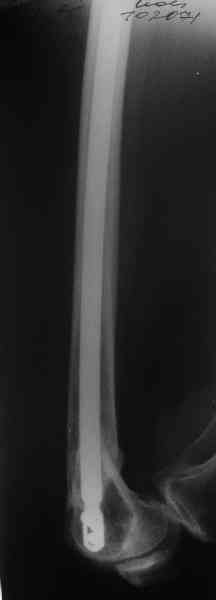

А в чем проблемы? Пример в приложении.

I> Насчет снимка Вами представленного - смотрится оч красиво, еще бы на

I> функцию узнать...

В приложении функциональные снимки в 3 мес. и в 1 год.